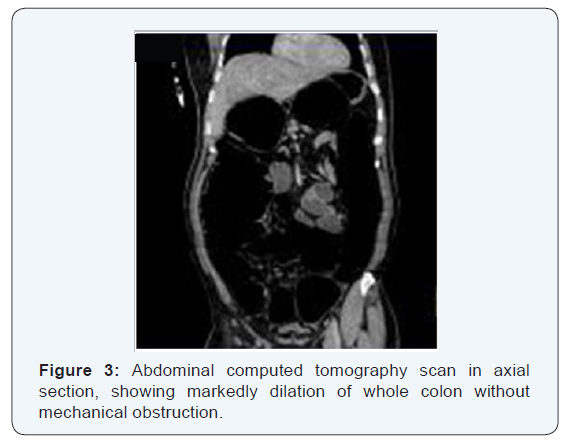

A 52-year-old Moroccan man from, without history admitted to our service for intracranial hypertension syndrome. The clinical examination revealed a cerebellar syndrome. CT scan and MRI angiography showed a hemorrhagic stroke of brain stem without vascular anomaly. One day later He developed abdominal discomfort. On examination, he had a distended abdomen, diffuse tenderness without rebound pain and reduced bowel sounds, but no abdominal mass or peritoneal signs. The patient had no history of metabolic, cardiovascular or pulmonary disease, abdominal or pelvic operations, abdominal cancer, intra-abdominal inflammation or abdominal trauma.He did not take other concomitant medication. He was afebrile, and results of blood tests were unremarkable. Plain abdominal radiography showed diffuse bowel loop dilation (Figure 1), and computed tomography showed marked bowel loop dilation and colonic gas, without obstructive masses or ischemic bowel lesions (Figures 2-4). We diagnosed acute pseudo-obstruction of the colon (Ogilvie syndrome). Nasogastric decompression and discontinuation of oral intake did not relieve our patient’s abdominal pain.

Ischemia or perforation is the feared complication of ACPO; spontaneous perforation has been reported in 3% to 15% of patients with a mortality rate of 50% or higher [9] Depending on the severity of the underlying illness, the overall mortality may be as high as 25% to 31% [10]. Abdominal x-ray plays a crucial role in the diagnosis and management of ACPO. It shows a massively dilated colon with minimal or no distention of the small intestine [5] Although CT with oral and intravenous contrast medium is not essential for the diagnosis, it may be helpful in excluding the presence of frank perforation, obstruction, and toxic megacolon. On CT images, there is normal haustral marking, lack of gas in the distal colonic segments, and marked dilatation of the colon in the absence of any obstructive lesion [10]. Evidence of rapid cecal dilatation or a cecal diameter larger than 11 to 13 cm on abdominal x-ray radiographs has been associated with increased risk of cecal ischemia, necrosis, and perforation [5,7,11]. No consensus exists regarding the minimal cecal diameter required for the diagnosis; the most commonly agreed value is 9 cm, in our case this diameter is 13 cm. The main focus of management of Ogilvie’s syndrome relates to treating the underlying disorder and correcting any biochemical abnormalities. Initial management in acute colonic pseudo- obstruction usually involves confirmation of the syndrome. Subsequently, care can be divided into several phases. These phases include conservative, pharmaceutical, endoscopic and surgical management, all of which involve nursing input and specific nursing interventions most cases of acute colonic pseudo-obstruction respond to conservative management Studies have suggested that intravenous administration of neostigmine, an acetylcholinesterase inhibitor, causes rapid colonic decompression in people with Ogilvie’s syndrome [12]. It is speculated that the rationale of the pharmacological approach is based on the theory that acute colonic pseudo-obstruction results from parasympathetic dysfunction or excessive sympathetic stimulation. Neostigmine 2mg given intravenously over three to five minutes rapidly decompresses the colon in people with acute colonic pseudoobstruction who have failed to respond to conservative treatment [13]. In our case, after intramuscular injection of neostigmine colonoscopic decompression, defecation occurred approximately 2 h later. Recurrence after medical treatment is 20–50% [13] for recurrences; neostigmine may be a useful therapeutic agent, especially for uncomplicated cases.